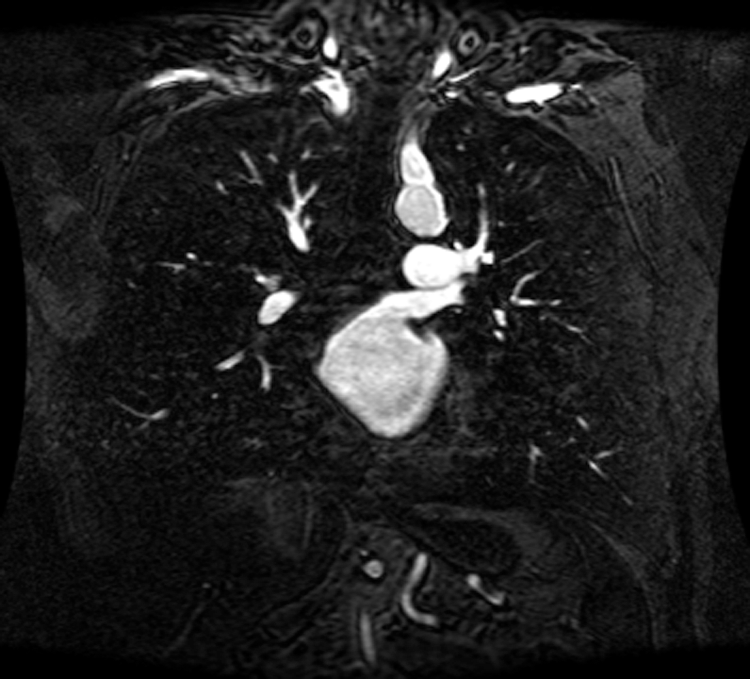

An intelligent-MRI VLC has been implemented for MRI image transmission using VLC and RF interference is eliminated. The proposed intelligent-MRI VLC system is experimentally analyzed using MRI images of different sizes i.e., 100, 115, and 120 KB respectively. These MRI images of the chest are downloaded from a medical database physionet.org. The downloaded MRI images are of T1 weighted type, which has grey matter darker than white matter was used for the proposed work. Images are acquired using Image Acquisition (IMAQ) in LabVIEW and transmitted using visible light in an indoor environment. The downloaded MRI images of various sizes are shown in Figs. 13–15.

Figure 13: 100 KB MRI image

Figure 14: 115 KB MRI image

Figure 15: 120 KB MRI image